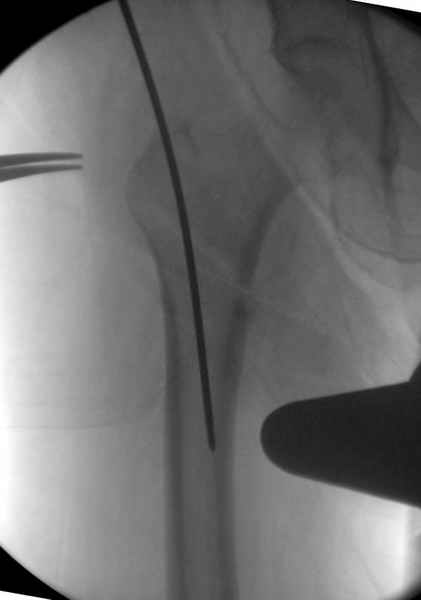

Здесь сканнированные снимки импланта и операционные снимки больной.

На этом снимке процесс компрессии нижним болтом.